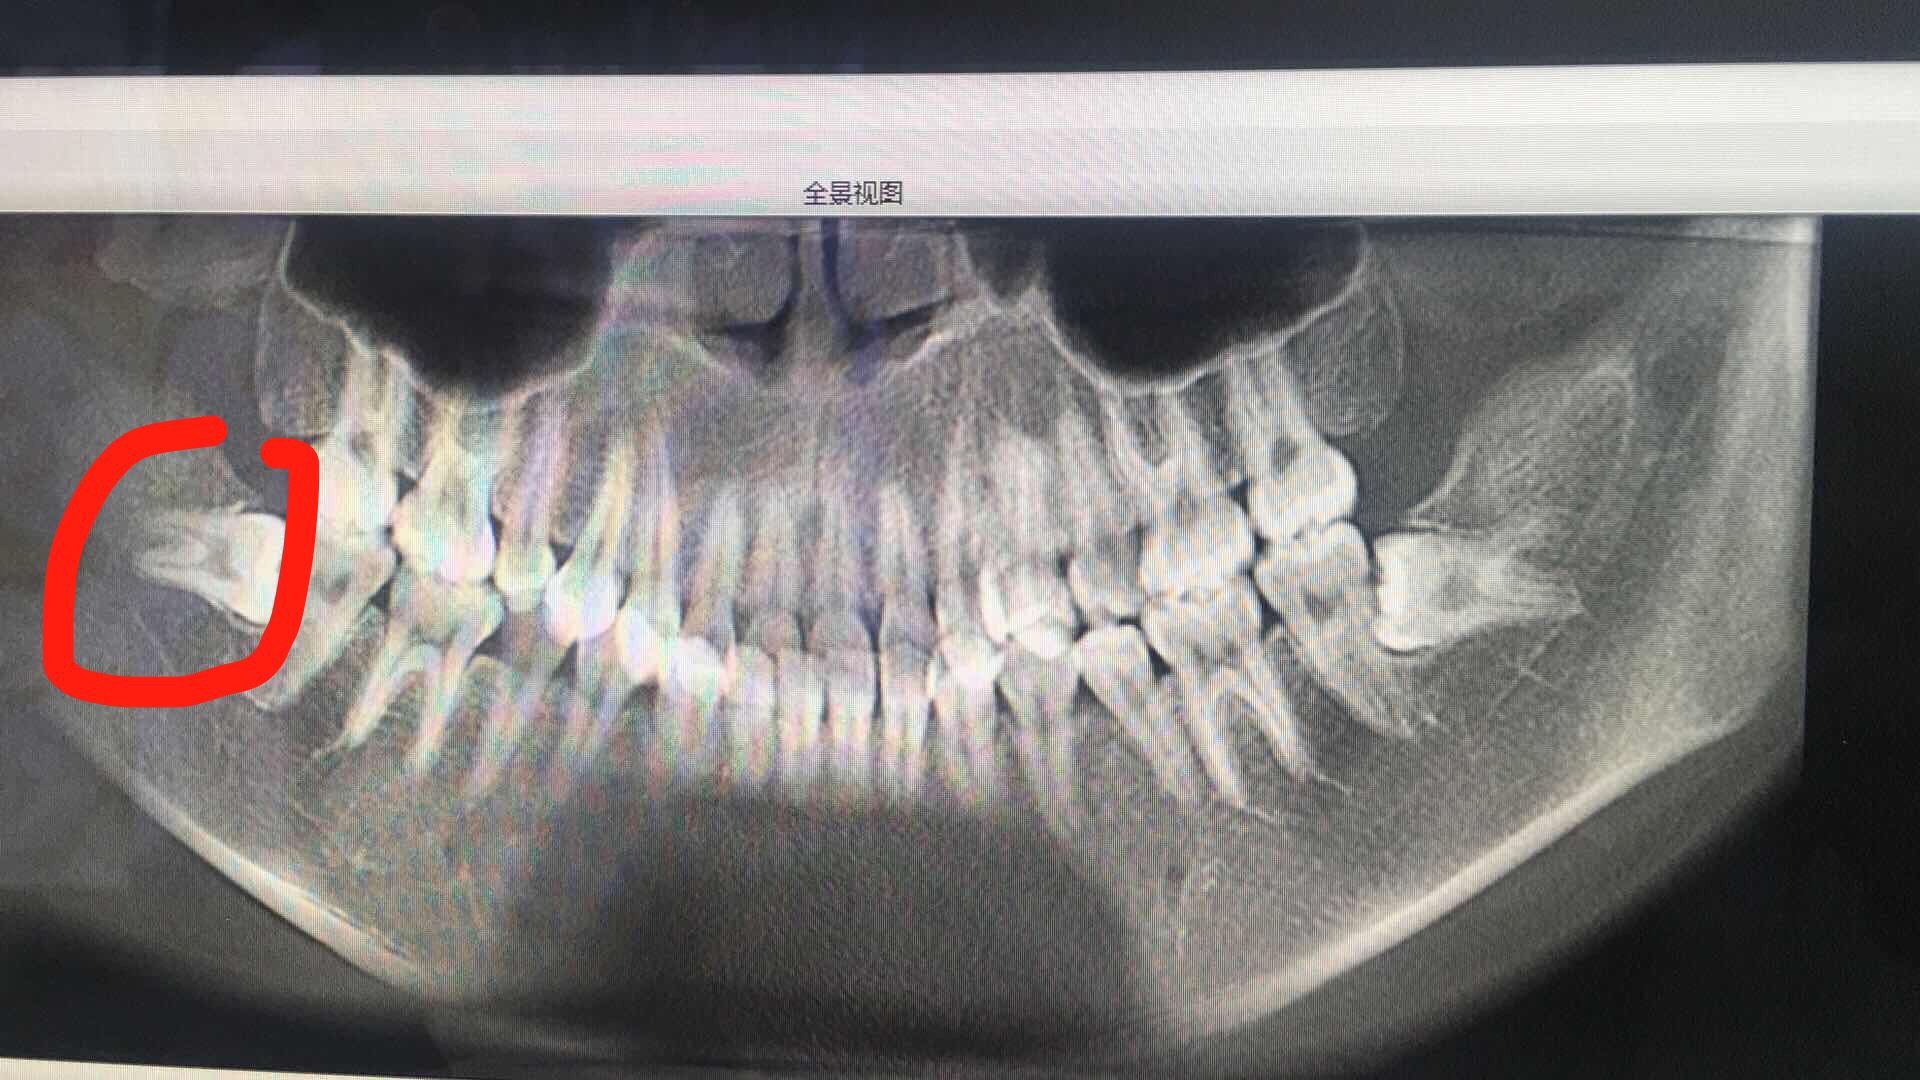

3月28号,拔了一侧智齿(红色圈出来的)

横向阻生的骨埋伏

去了部分骨,缝了几针。最多用了10分钟时间吧,麻药过去后有点小疼就是脸肿了,不影响吃东西。